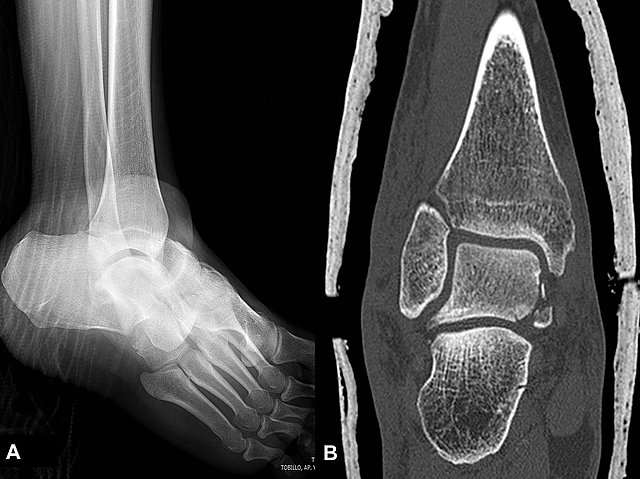

• Tomografía computarizada (TAC) y Resonancia magnética

Tomografía computarizada (TAC) y Resonancia magnética

Buscan localizar la lesión en el encéfalo humano vivo,

La tomografía muestra secciones del encéfalo usando rayos X, mientras que la resonancia muestra secciones del encéfalo utilizando un campo magnético y ondas de radio.